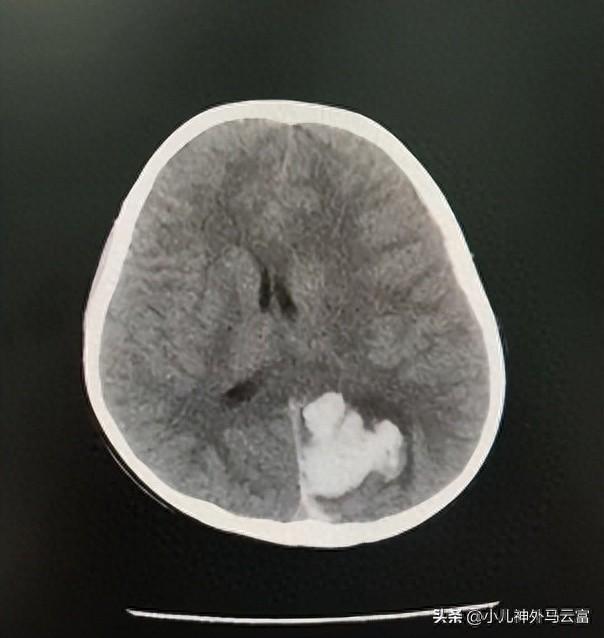

患兒小胡,嘔吐1天餘,CT提示左側頂枕葉出血伴血腫形成;左側額頂顳葉硬膜下出血,大腦鐮旁出血。可見中線移位。

提示:1.顱內出血(非創傷性)2.腦疝

根據診斷結果,湖北省婦幼保健院小兒神經外科團隊專家緊急進行討論,考慮患兒顱內出血量大,已發生腦疝,決定急診行神經內鏡下血腫清除術。

術後CT